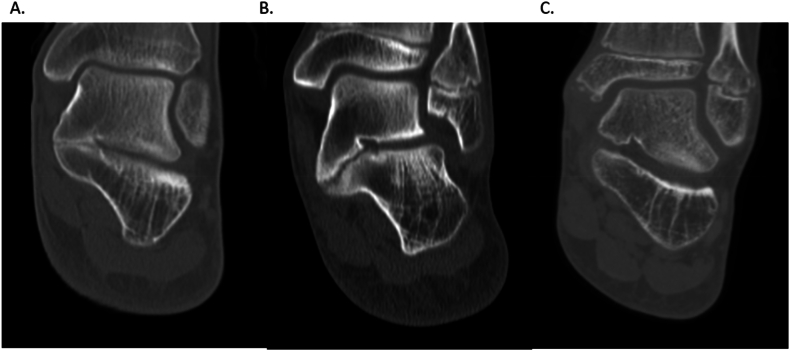

Results: Twenty-seven patients (16 male), average age 13.9 ± 2.4, met study criteria. TCCs were located on the right lower extremity in 10/27 cases. Sixteen/twenty-seven coalitions were horizontal, 10/27 was down sloping, and 1/27 was upsloping relative to the joint line. Substantial agreement was achieved between three raters (mean average measures intraclass correlation 0.781). The mean coalition length in the sagittal plane was 21.2 ± 6.0 mm, covering 49.6 ± 23.2% of the talar length.

Key concepts: (1)To date, very little in the way of intraoperative planning for TCCs has been proposed in the literature, even though advanced imaging has been widely used preoperatively.(2)Our method of mapping coalitions on preoperative CT may assist with intraoperative resection. Additionally, this method demonstrates the three-dimensional variety that can be expected in surgical excision of these coalitions.(3)Neither the medial to lateral depth nor the distance proximal from the sustentaculum talus was uniform as the coalitions were thickest centrally and tapered both proximally and distally.